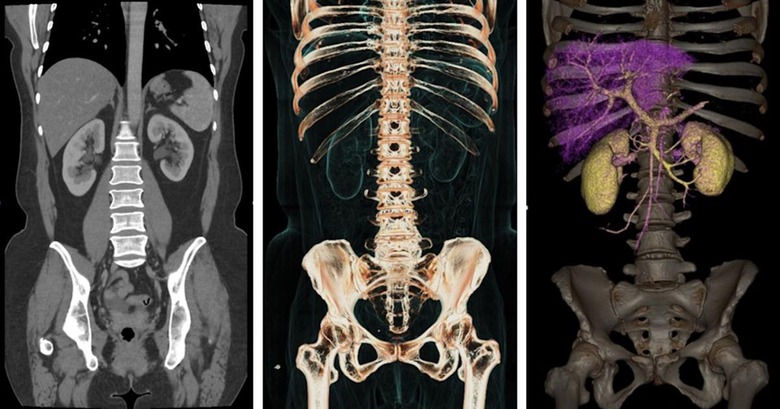

Deep learning tech is making itself at home in hospitals by helping radiologists examine medical scans for just a buck per image. Now, GE Healthcare is bringing that AI tech directly to the scanners, thanks to partnerships with NVIDIA and Intel. It announced that it will update 500,000 of its medical devices around the world with NVIDIA AI tech, most notably its Revolution Frontier CT scanner (below). The tech "is expected to deliver better clinical outcomes in liver lesion detection and kidney lesion characterization because of its speed," GE wrote in a press release.

Clinical diagnosis has dramatically improved thanks to improved imaging via incredibly advanced MRI, CT and other machines, but there's a downside to that tech. It generates up to 50,000 terabytes of data, per hospital, but only three percent of that is analyzed or even tagged, says GE.